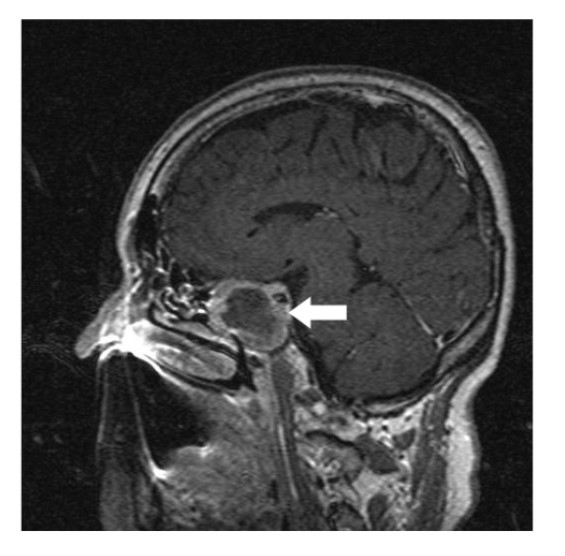

A 64-year-old lady presented to the outpatient department with complaints of headache and right eye blurring of vision for one month. Neurological examination revealed that bitemporal hemianopsia and impairment of visual acuity. Findings from fundus examination were within normal limits. Rest of the brain appeared unremarkable. Endocrine evaluation was normal. Results of renal function tests, liver function tests and haemogram test were within normal limits. A clinical diagnosis of non-secretory pituitary adenoma was made. Magnetic resonance imaging showed a well-circumscribed contrast-enhancing lesion in the sella (Figure 1, Figure 2). The patient underwent an endoscopic endonasal/transsfenoidal surgery in the supine position and total lesion resection was peformed. Intraoperatively, the lesion was found to be yellow colour, soft and avascular and it was removed totally until the sella turcica was visualized (Figure 3).In histopathologic examination septate hyphae were observed between inflammatory cells, Grocott staining is positive, but acid-fast stain for acid-fast bacilli (AFB) was negative. Histopathological findings suggest that infection of Actinomyces (Figure 4, Figure 5). We performed to patient consulted by patients to infectious diseases clinic. Patients underwent intravenous 6x2 gr ampicillin for four weeks.Then oral 4X500 mg amoxicillin treatment is planned a for at least 6 months. Patient did not have any deficits in the next six months.

Figure 1.White arrow shows on sagittal section of MRI that a well-circumscribed contrast-enhancing lesion in the sella

Preoperative diagnosis of pituitary abcess is difficult because the presenting symptoms in these patients are similar to that in patients with pituitary adenomas 4. The most common symptoms are headache, vision disturbances and endocrinological abnormalities 5. Magnetic resonance imaging is the best imaging modality for sellar abscess and the features include a hypo- or iso-intense sellar mass on T1-weighted sequences and a hypointense mass on T2-weighted sequences pituitary abscesses may be divided into primary and secondary types. Primary pituitary abscesses occur within a previously healthy gland, while secondary abscesses arise within an existing lesion, such as an adenoma, craniopharyngioma, or Rathke's cleft cyst. Secondary abscesses share radiologic characteristics with the lesions from which they arise. The typical primary pituitary abscess gives the same or slightly lower signal than brain on T1-weighted images, and could be mistaken for a solid mass or presumed to represent a pituitary adenoma. Contrast-enhanced images are useful, demonstrating absence of central enhancement, suggesting a fluid or necrotic center 6.Actinomyces brain abscess is usually diagnosed based on the contrast enhancement on the periphery as in this case.Also MRI spectroscopy findings are the described in actinomyces infection 7, 8.